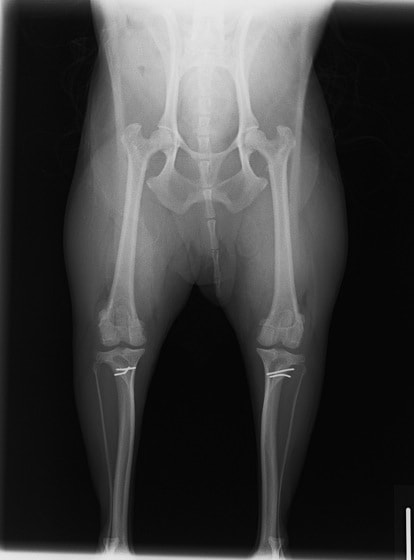

■ 症例24 キャバリア 7か月

左右膝蓋骨内方脱臼(左:グレードⅣ 右:グレードⅢ)

以前から左右後肢の跛行が認められ、整形外科学的検査・レントゲン検査により左右の膝蓋骨脱臼が認められた。症状が重度である左膝の膝蓋骨脱臼整復術を行った。外科手技は縫工筋及び内側広筋の解放、脛骨粗面の外側転位、滑車ブロック形造溝術、内外側関節方の縫縮を実施した。術後一か月時点で、左の膝蓋骨は安定しており経過は良好である。

本症例は成長期における重度の膝蓋骨脱臼であり、術後の再発の可能性もあるため、経過をしっかりと観察していく必要がある。また、今回手術を実施していない右膝に関しても経過を観察し、手術を検討していくこととする。